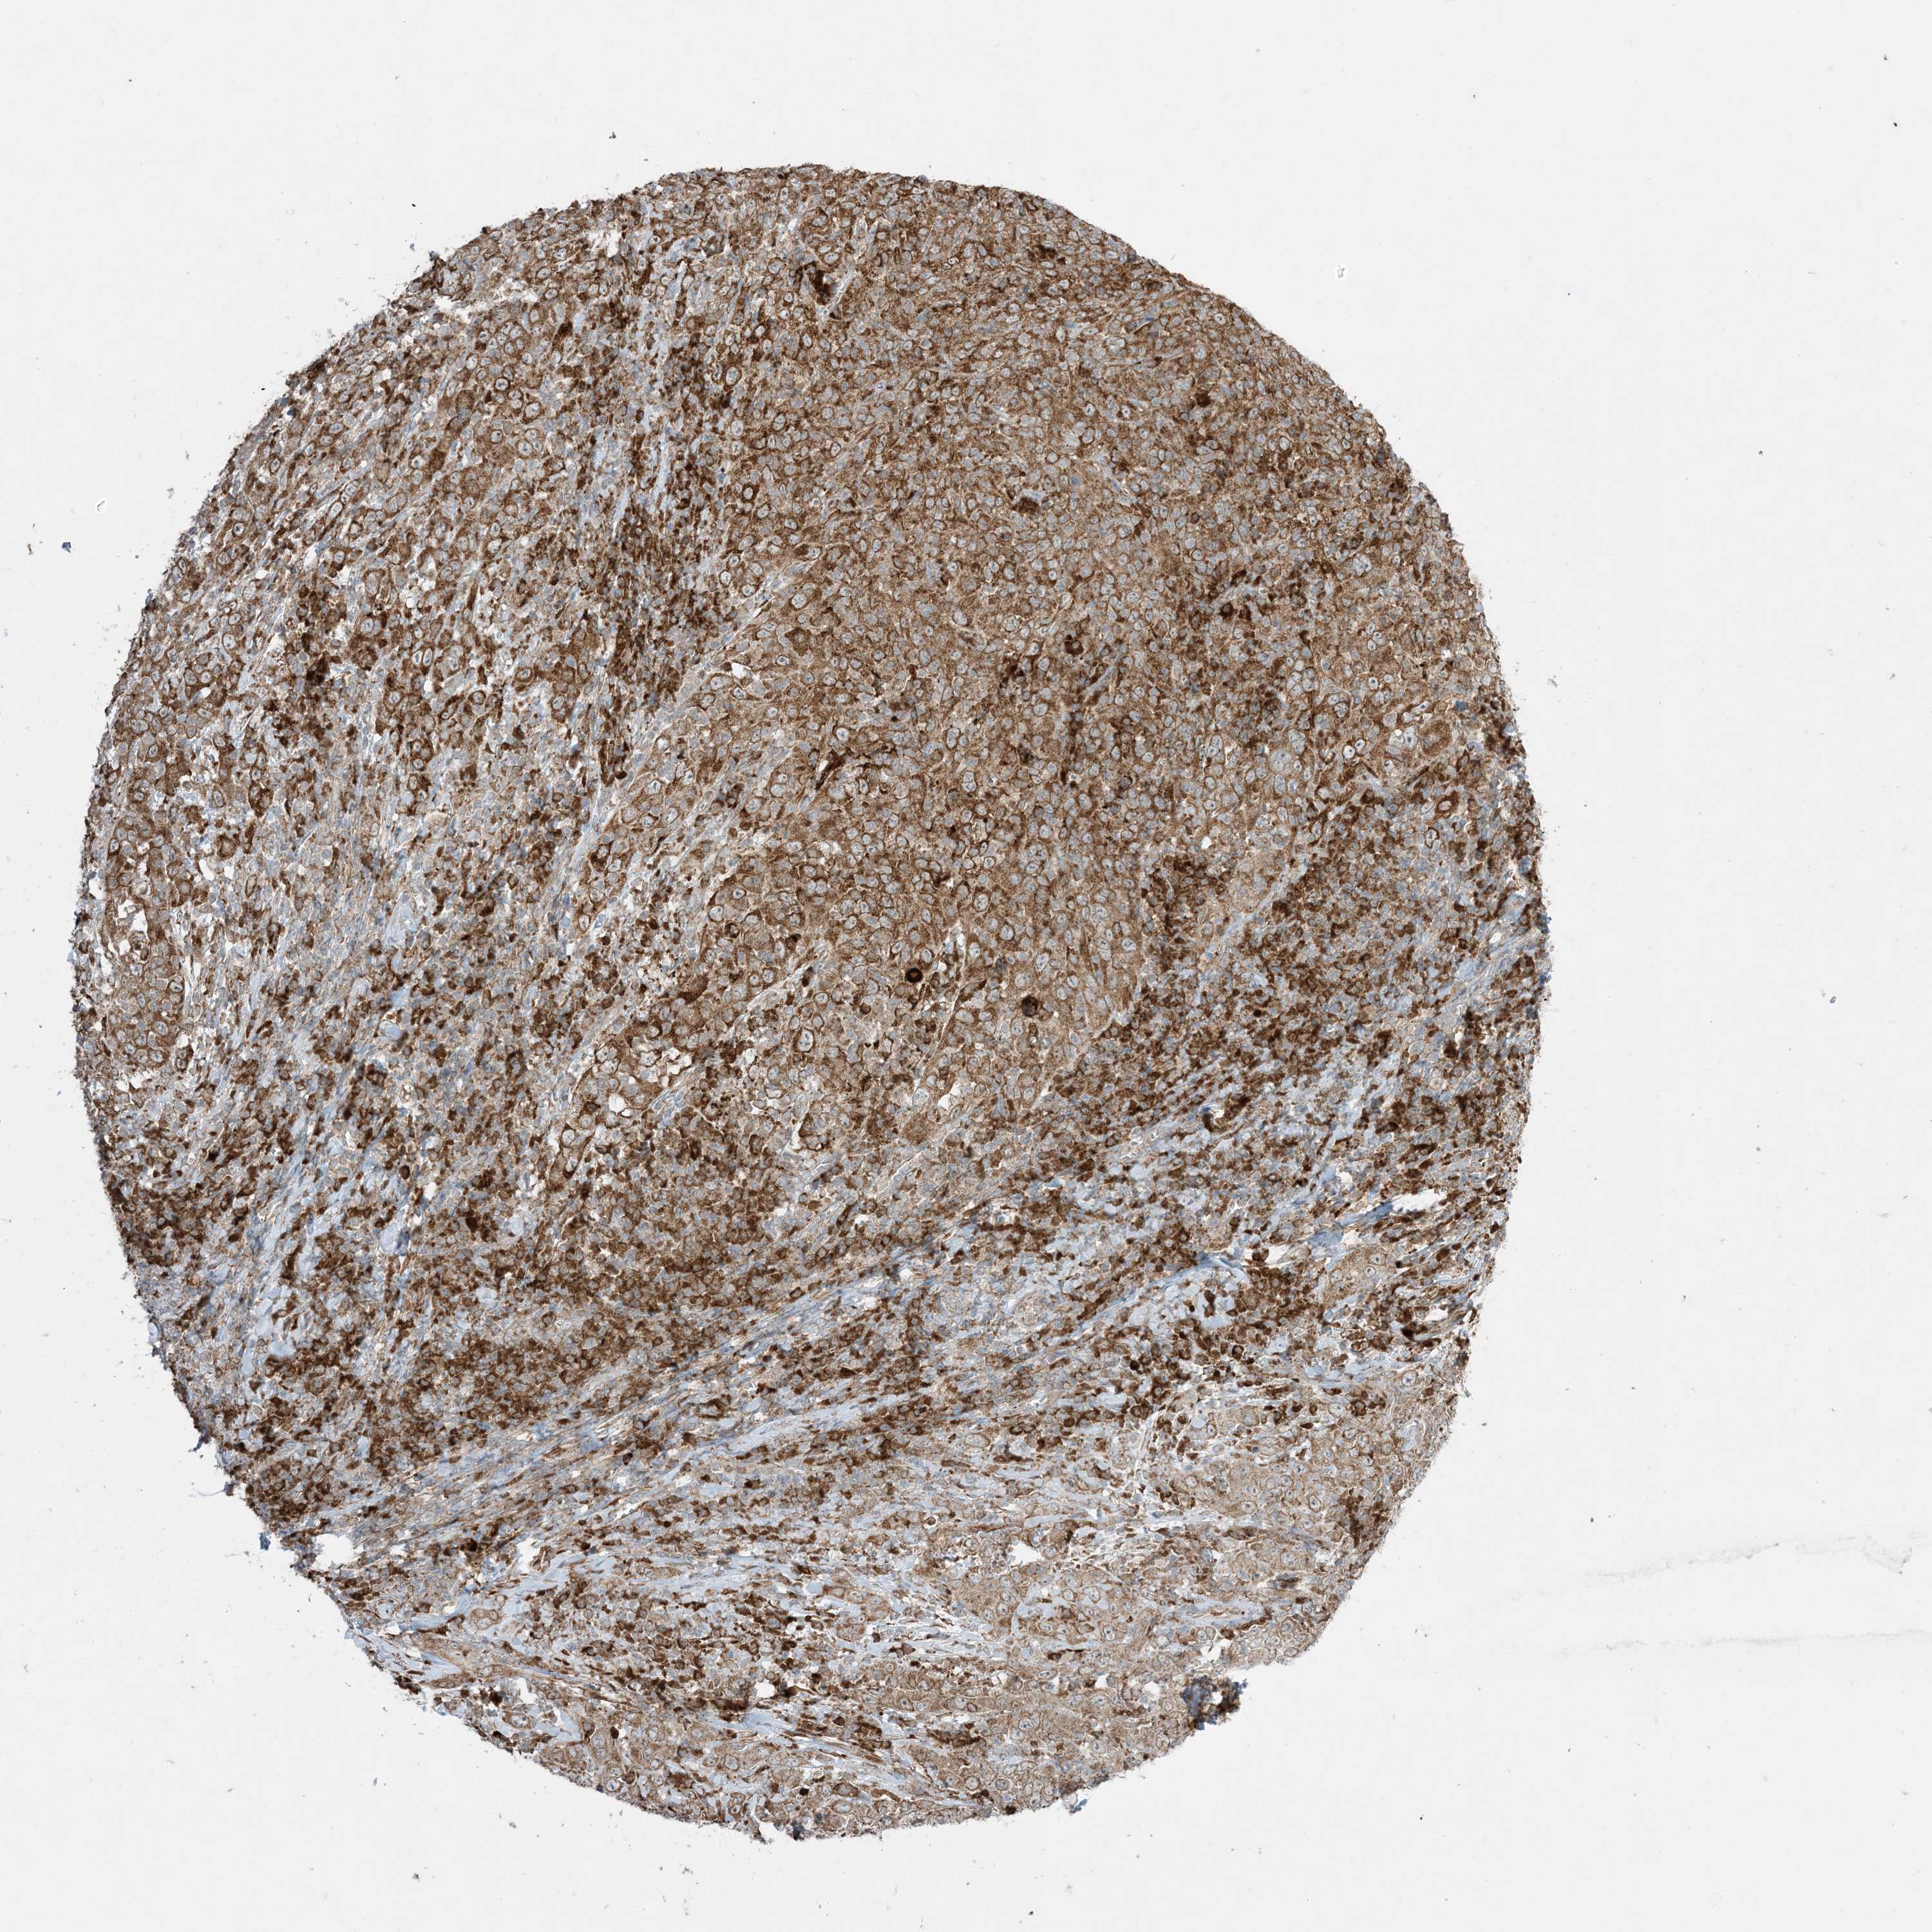

CERVICAL CANCER - Protein expressioni

A mouse-over function shows sample information and annotation data. Click on an image to view it in a full screen mode. Samples can be filtered based on level of antibody staining by selecting one or several of the following categories: high, medium, low and not detected. The assay and annotation is described here.

Note that samples used for immunohistochemistry by the Human Protein Atlas do not correspond to samples in the TCGA dataset.

Antibody stainingi

Antibody staining in the annotated cell types in the current human tissue is reported as not detected, low, medium, or high, based on conventional immunohistochemistry profiling in selected tissues. This score is based on the combination of the staining intensity and fraction of stained cells.

Each image is clickable and will lead to virtual microscopy that enables deeper exploration of all samples and also displays staining intensity scores, fraction scores and subcellular localization as well as patient and tissue information for each sample.

Antibody HPA001536

Antibody CAB035996

Staining

High

Medium

Low

Not detected

Intensity

Strong

Moderate

Weak

Negative

Quantity

>75%

75%-25%

<25%

None

Location

Nuclear

Cytoplasmic/membranous

Cytoplasmic/membranous,nuclear

Squamous cell carcinoma, NOS

Adenocarcinoma, NOS